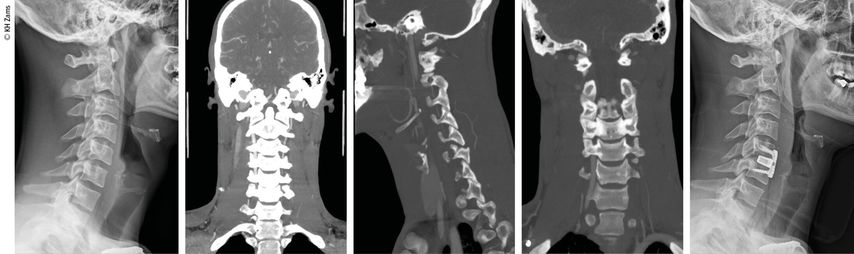

Abb. 2: Fallbeispiel: Mann, 57a, Z.n. Fahrradsturz, stabile Fraktur des Proc. artic. C2 r. mit Dissektion der A. vertebralis r. mit asymptomatischem Substanzdefekt im hinteren Stromgebiet (cMRT), Heparintherapie initial, anschließend APT

Abb. 3: Mann, 30a, Z.n. Snowboardsturz, Rotations-/Subluxationsverletzung C5/6 mit Dissektion der A. vertebralis r.; Zervikobrachialgie mit sensiblem Defizit; OP unter Heparintherapie, APT für 3 Monate